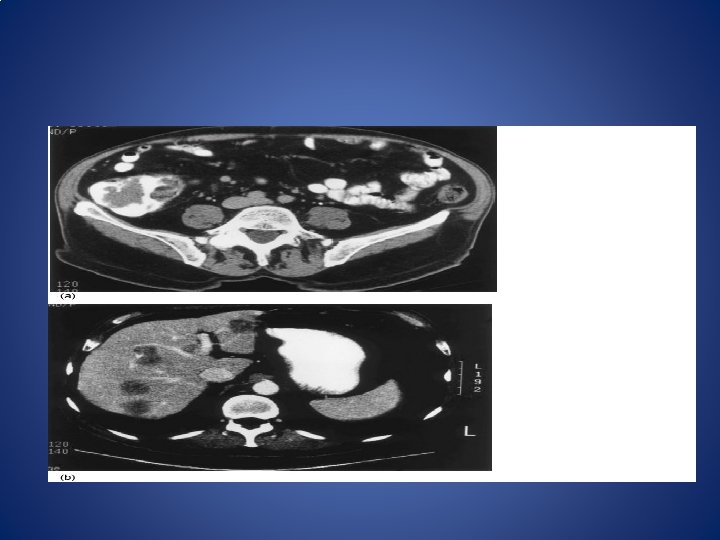

SPREAD • Local spread • Initially circumferentially and later spreads out to muscular coat and peri-rectal tissue. • Then to prostate, bladder, seminal vesicles in males and ureters and vagina in female. • Posteriorly into sacrum and sacral plexus. • LYMPHATIC SPREAD • Along the colonic lymph nodes • In mid-rectum----rectal and mid-rectal nodes

• VENOUS SPREAD • Liver 35%, lungs 20%, adrenas 10% • PERINEURAL SPREAD

STAGING • MODIFIED DUKE’S STAGING • A. growth limited to rectal wall • B 1. growth extending into extra rectal tissue but no lymph nodes spread • B 2. invading muscularis mucosa • C. lymph nodes secondaries • D. distant spread to liver, lungs, bones, brain